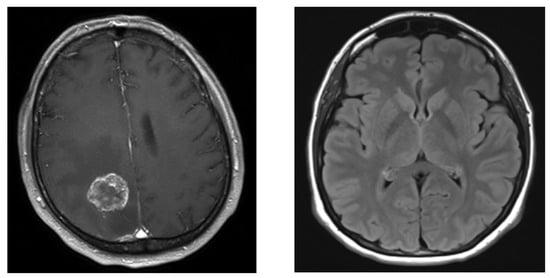

- Example 1: In this example, MRI Brain data were used from the Kaggle repository [21]. A brain tumor is an abnormal growth of cells in the brain. These tumors can be categorized as either benign, which means they are noncancerous and typically grow slowly, or malignant, which means they are cancerous, grow rapidly, and can invade surrounding tissues. The dataset contains 253 MRI images with 155 malignant and 98 benign binary classes. Figure 5 displays the MRI images of the malignant and benign cases.

Figure 5.

MR images of two classes: malignant (left) and benign (right) tumors.